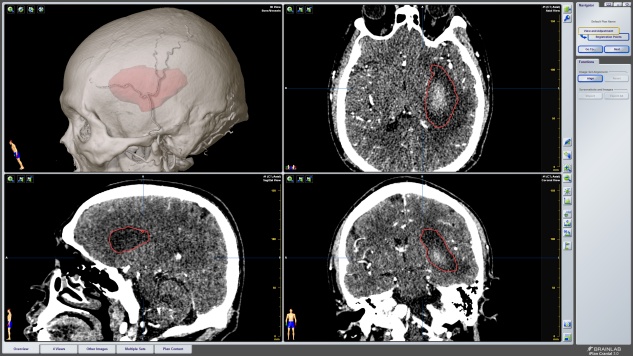

经过精密的术前准备与讨论,侯立军主任根据独创的国际创新理念与术式,为老杨实施了机器人辅助下枕部入路颅内血肿穿刺引流术。手术机器人的机械臂经过精准的计算与术前计划,准确的避开功能区,穿刺到达血肿,将血肿完全吸除。整个手术过程仅半小时,出血量微乎其微。

术前设计手术规划

左:术前设计的精准穿刺路径

右:术后可见血肿完全清除